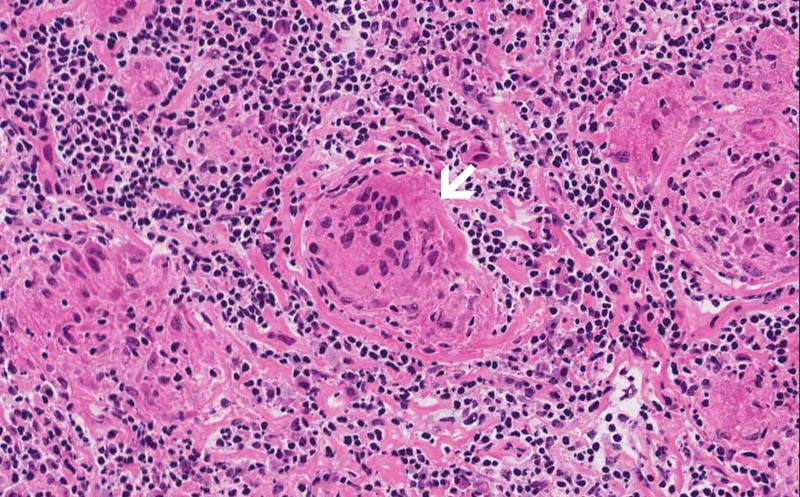

Area 2: Asteroid bodies (arrow) can be seen in this giant cell.

• Granulomas are roughly round to oval to irregular collections of histiocytes often with mutinucleated giant cells. They can be seen in multiple types of disease processes that include sarcoidosis, fungal infection, mycobacterial infections, berylliosis, foreign body, granulomatous changes of neoplasms particularly lymphomas and germ cell tumors, Wegerner's granulomatosis, and other conditions.Granulomatosis in sarcoidosis is usually non-necrotizing but necrosis may occur. Inclusions such as Asteroid bodies (Area 2) and Schaumann bodies can be seen in sarcoidosis. These inclusions are suggestive, however, non-diagnostic for sarcoidosis.